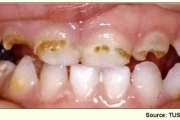

Lutipudelikaariese kahjustused

Lutipudelikaaries